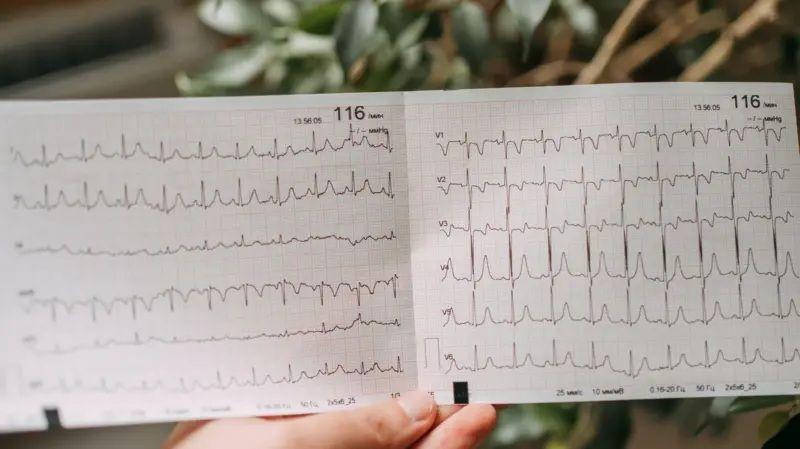

ڈاکٹر پکھمود نے تین دن پہلے ای سی جی یعنی الیکٹرو کارڈیوگرام ٹیسٹ کروایا تھا جو کہ نارمل تھا۔ ٹیسٹ نارمل ہونے باوجود ان کا دل کے عارضے کے باعث مر جانا سب کے لیے حیران کن تھا۔

ڈاکٹر پکھمود نے تین دن پہلے ای سی جی یعنی الیکٹرو کارڈیوگرام ٹیسٹ کروایا تھا جو کہ نارمل تھا۔ ٹیسٹ نارمل ہونے باوجود ان کا دل کے عارضے کے باعث وفات پانا سب کے لیے حیران کن تھا۔

امراض قلب کے ماہرین کا کہنا ہے کہ ای سی جی کا درست آنا ہی دل سے متعلق بیماریوں کی جانچ کا واحد معیار نہیں ہے۔

ای سی جی ایک سادہ ٹیسٹ ہے جو دل کی برقی سرگرمی کو ریکارڈ کرتا ہے۔ یہ ڈاکٹروں کو دل کی تال اور برقی سگنل کی جانچ کرنے کے قابل بناتا ہے۔

ای سی جی میں سینے اور ہاتھوں کے گرد الیکٹروڈ نامی سینسر لگایا جاتا ہے جس کی مدد سے دل کی دھڑکن سے پیدا ہونے والے برقی سگنل کا پتا لگایا جا سکتا ہے۔

انھوں نے بی بی سی ہندی کو بتایا کہ ’دل کی بیماری کا پتہ لگانے کا واحد طریقہ ای سی جی نہیں ہے۔ 10 فیصد بھی نہیں۔‘

ای سی جی دل کی بیماری کی ابتدائی تشخیص کا ایک لازمی حصہ ہے۔ یہ عمل دل کے بنیادی اناٹومی اور برقی ترسیل کے نظام کا جائزہ لیتی ہے۔

اگر کسی ڈاکٹر کو دل کی بیماری کا شبہ ہو تو وہ ای سی جی ٹیسٹ تجویز کر سکتے ہیں۔ ایک ای سی جی ٹیسٹ اس بات کا تعیّن کرنے کے لیے ایک عام رینج دکھاتا ہے کہ آیا آپ کو دل کا کوئی مسئلہ ہے یا نہیں۔

کارڈیالوجسٹ ڈاکٹر مہیش پھلوانی اور شری کرشنا ہردیالیہ ناگپور کے ڈائریکٹر نے بی بی سی ہندی کو بتایا کہ ’ایک عام ای سی جی اس بات کی ضمانت نہیں دیتا کہ کوئی شخص کئی گھنٹے، مہینوں یا سالوں تک زندہ رہے گا۔ دل ایک ایسا عضو ہے جو متحرک ہے۔‘

’اس کے اندر بہت سی سرگرمیاں چل رہی ہیں اور ای سی جی ان کا اندازہ لگانے کا ایک طریقہ ہے۔‘

ڈاکٹر جواہرانی کا کہنا تھا کہ ’ای سی جی سے پتہ چل سکتا ہے کہ آیا ہارٹ اٹیک جیسا کوئی سنگین مسئلہ ہے یا نہیں۔ 65 سے 70 فیصد مریضوں میں ای سی جی پر علامات ظاہر ہوتی ہیں۔ لیکن اگر ہارٹ اٹیک معمولی ہو تو ای سی جی پر اس کا پتہ نہیں چل سکتا۔‘

ایسی صورت حال میں تقریباً ایک گھنٹے بعد دوبارہ ای سی جی کروانے کا آپشن موجود ہے لیکن ای سی جی کے ساتھ ساتھ خون کے ٹیسٹ اور امیجنگ بھی کرانی پڑے گی۔

ڈاکٹروں کے مطابق ای سی جی ایک اہم ٹیسٹ ہے کیونکہ یہ دل کے دورے کی تشخیص کی تصدیق میں مدد دیتا ہے۔ اس کے علاوہ یہ ٹیسٹ یہ تعیّن کرنے میں مدد دیتا ہے کہ آپ کو کس قسم کا دل کا دورہ پڑا ہے۔ اس کے ذریعے سب سے مؤثر علاج کرنے کا فیصلہ کیا جا سکتا ہے۔